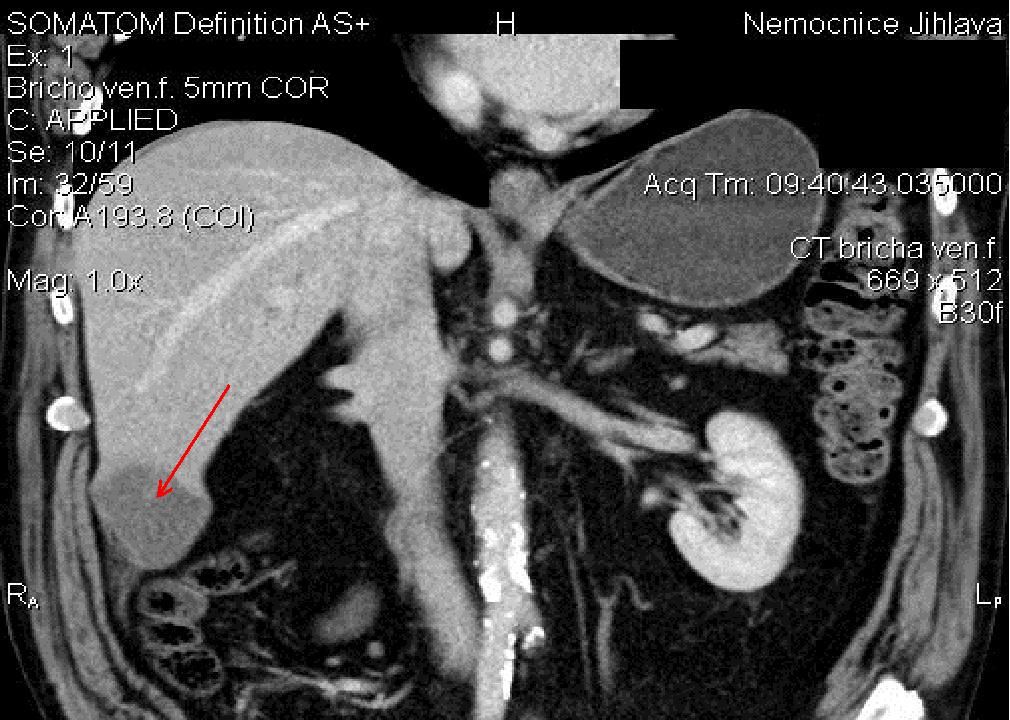

Šipka značí odstraněný nádor

Druhou výhodou je nižší ztráta krve. Při použití Habibova nože byly krevní ztráty do sto mililitrů, běžně to je při stejném výkonu a použití jiné metody až litr krve. S tím souvisí také kratší doba rekonvalescence pacienta, odpadají rizika spojená s podáním transfuzí. Oproti stávajícím metodám to znamená ušetření několika dní, které musel člověk strávit v nemocnici, a významné snížení rizika dalších komplikací.